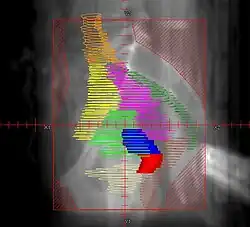

Example of a lateral radiation therapy treatment field for Stage IB2+ Cervix used at Tufts/Brown residency program. Actual patient contours should guide field design and AP/PA vs. 4F decision.

• Superior border: same as AP field

• Inferior border: same as AP field

• Anterior border: ~1cm anterior to symphysis pubis

• Posterior border: cover entire sacrum to ensure coverage of presacral lymph nodes

• Red: cervix; Blue: uterus; Khaki: bladder; Brown: rectum

• Orange: common illiac LNs; Yellow: external illiac LNs; Light Green: obturator LNs; Purple: internal illiac LNs; Dark Green: presacral LNs